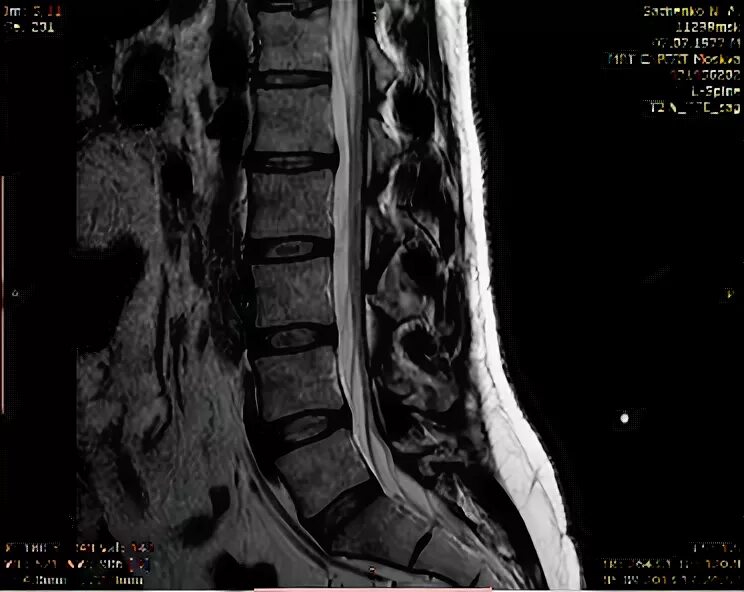

Протрузии дисков с3 с7